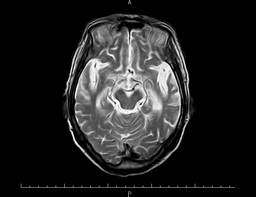

之后,医生为殷阿姨完善了其他检查,颅脑海马+MRA显示:1.双侧基底节区多发腔梗灶;2.脑白质变性;3.幕上(包括双侧海马)弥漫性脑萎缩,以左侧颞叶为著; 4.脑MRA检查提示脑动脉粥样硬化(图一)。颅脑ASL提示:全脑3D-ASL序列检查提示左侧额颞顶枕叶及右侧颞顶枕叶多发稍低灌注区,以左侧大脑半球为主(图二)。

头颅MRI T2图一 MRI FLAIR 图一